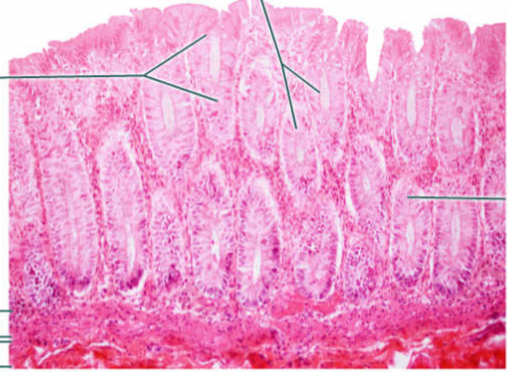

A

Mucosa: simple columnar epithelium with microvilli

B

Submucosa

C

muscularis mucosa

Area

Small intestine

E

simple columnar epithelium with goblet cells and microvilli

F

Villi

G

Lamina propria